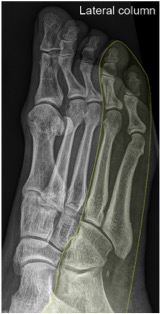

• Lateral

• 4th + 5th metatarsals

• cuboid

• calcaneus